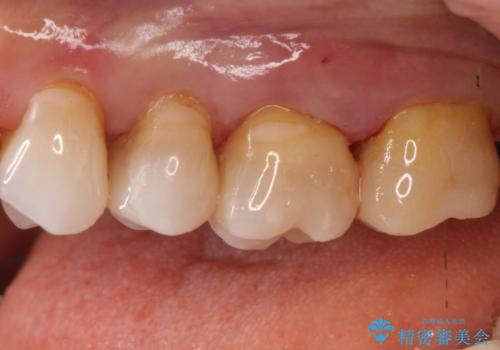

【メタルフリー】セラミックインレーによる治療

- 昔入れた銀歯のやりかえを主訴に来院されました。

セラミックインレーにて修復を行いました。

歯の強度を高めるためセラミッククラウンの提案もさせていただきましたが、患者様の希望でセラミックインレーにて修復を行なっております。